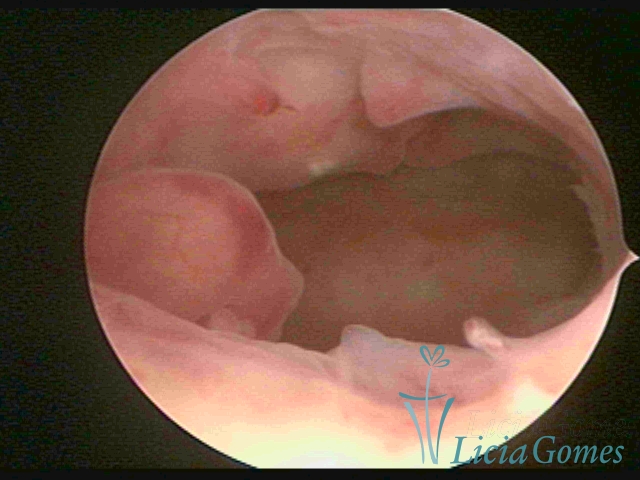

They may occur in a region of the uterine cavity considered as focal hypertrophy or occupy its whole extension, being called diffuse hypertrophy.

Polypoid hypertrophy is viewed when the endometrial growth is more pronounced and, since the space of the uterine cavity is limited, it presents the formation of folds or grooves, simulating pseudopolypoid or polypoid lesions.

Complex Hyperplasia has a pseudopolypoid aspect which resembles cerebroid tissue or with decidual reaction. The superficial vascularization is more evident, presenting vessels in the shape of corkscrew or spiral.

Atypical hyperplasia and histeroscopical aspect are similar to complex hypertrophy, also presenting vascularization with atypias. With the increase of the thickness of the superficial vessels, tissues in necrosis may also be found.